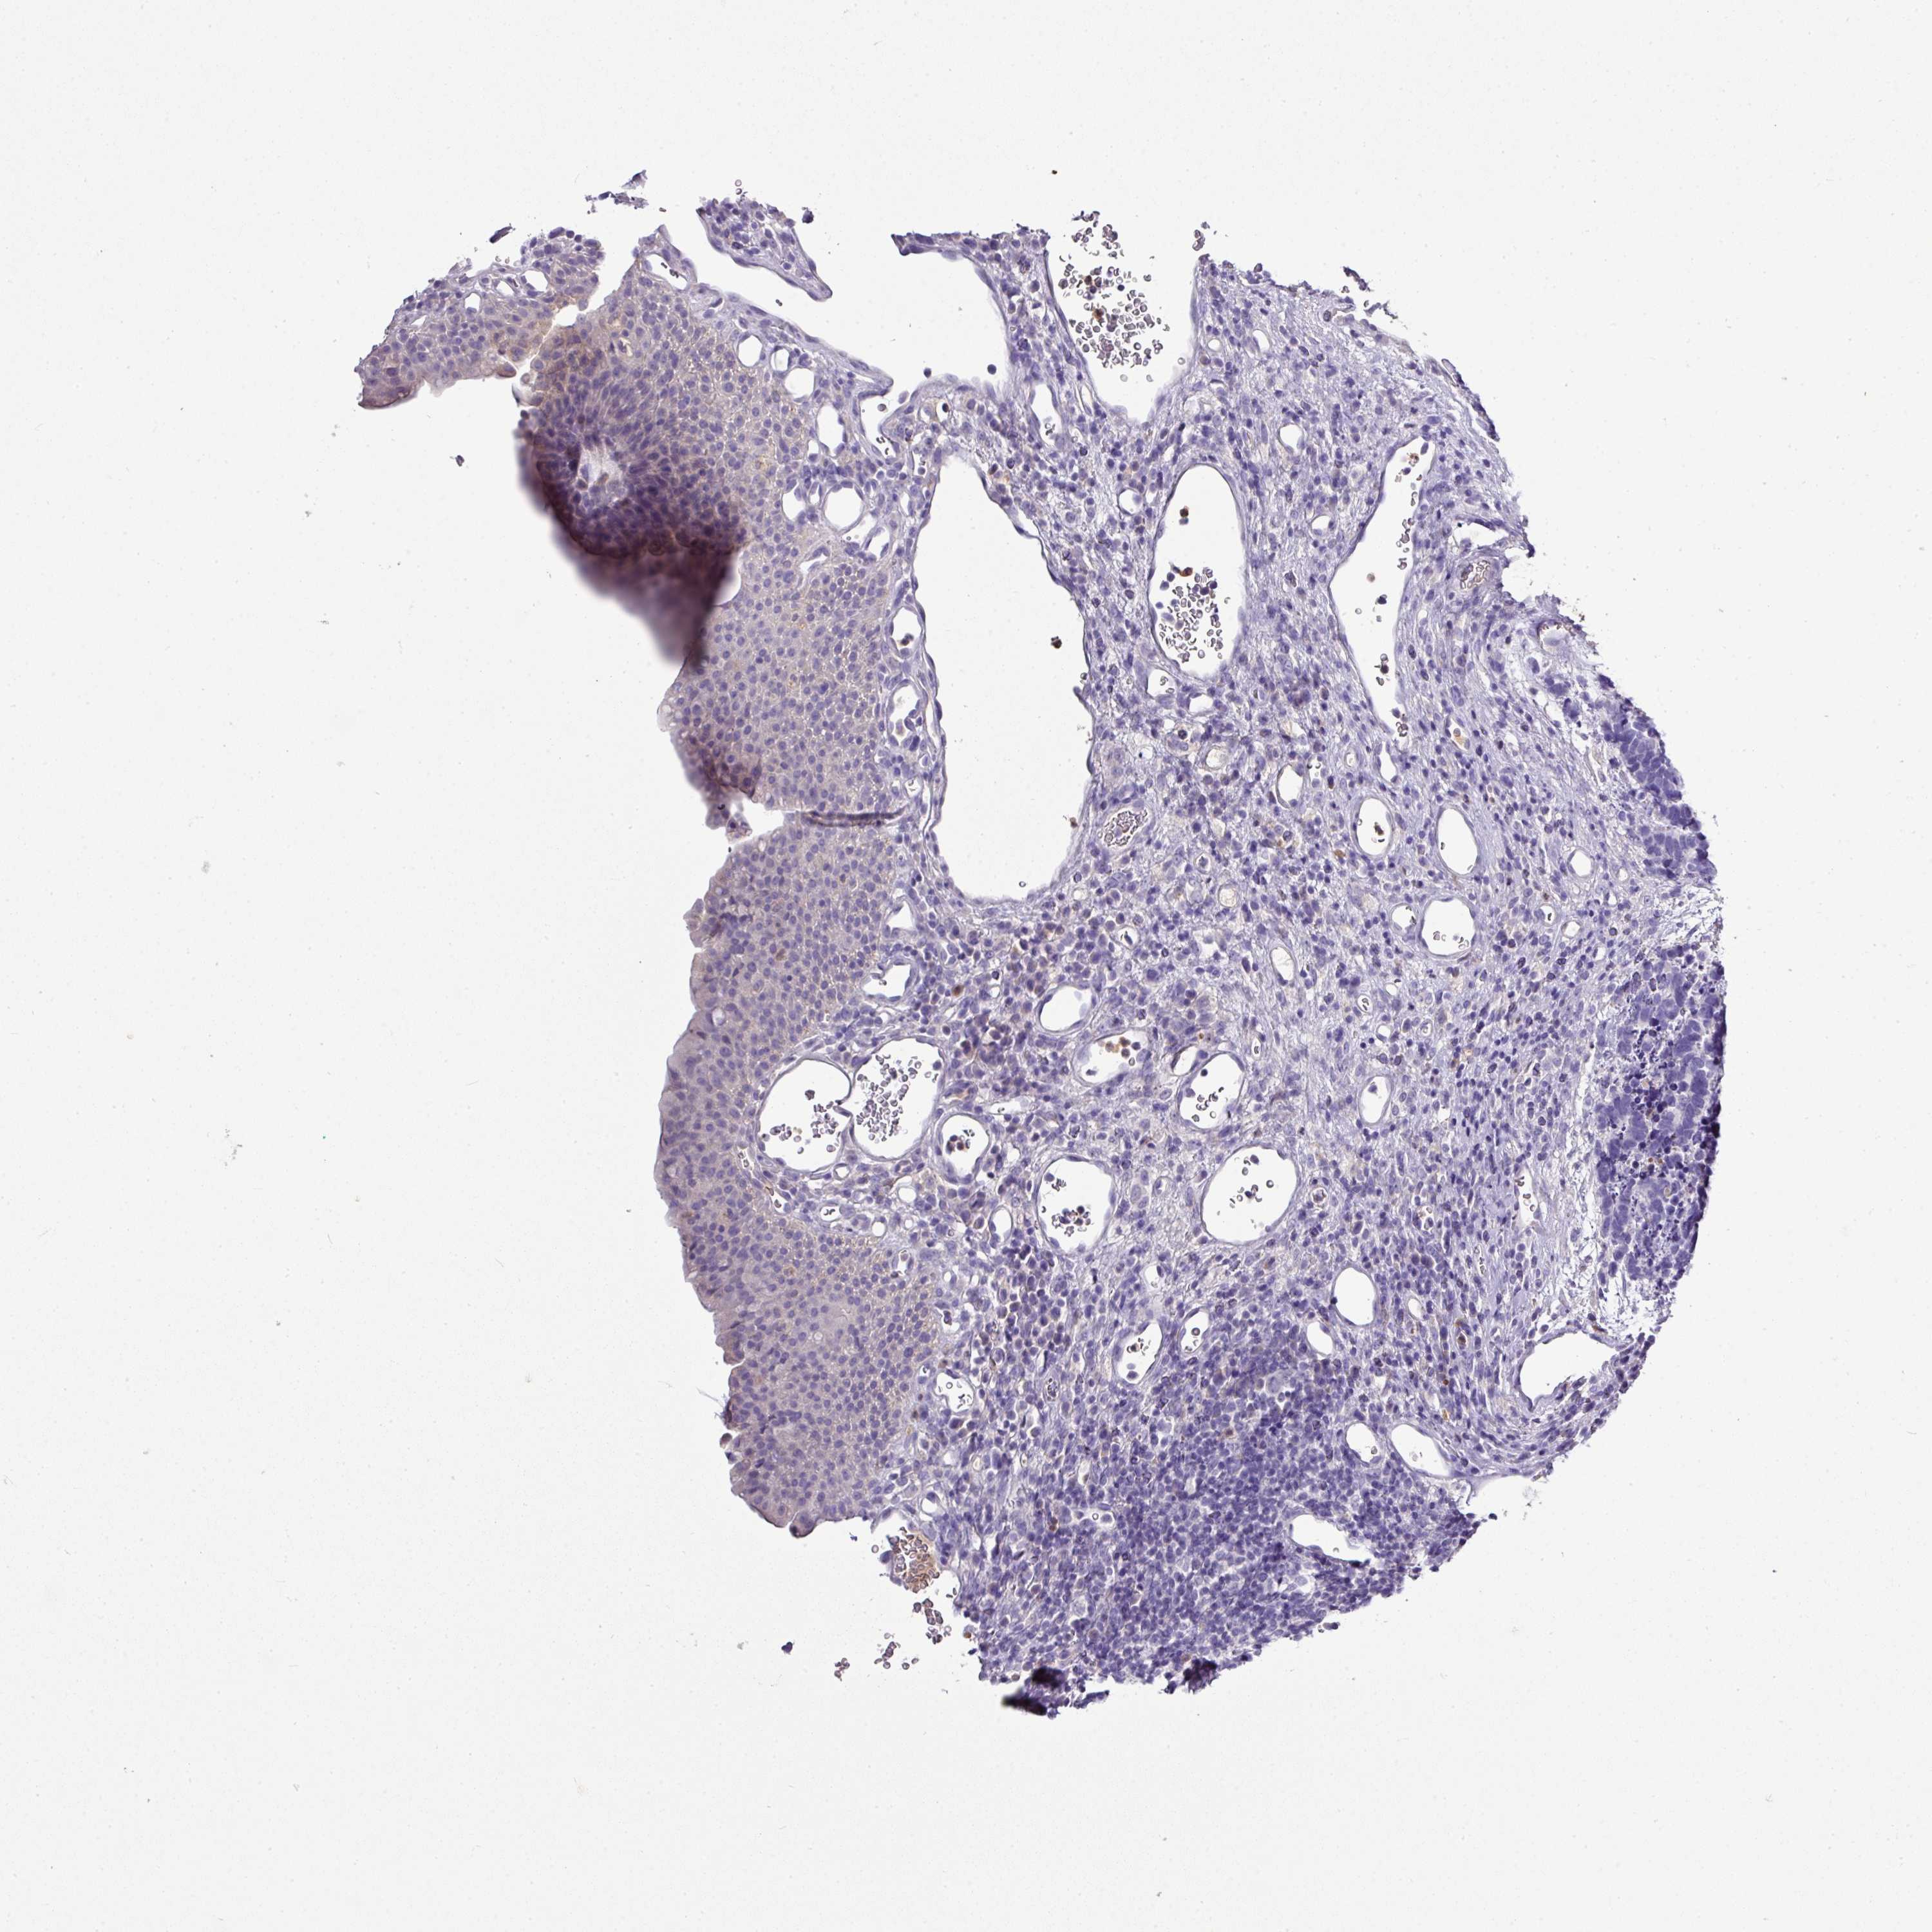

CARCINOID - Protein expressioni

A mouse-over function shows sample information and annotation data. Click on an image to view it in a full screen mode. Samples can be filtered based on level of antibody staining by selecting one or several of the following categories: high, medium, low and not detected. The assay and annotation is described here.

Each image is clickable and will lead to virtual microscopy that enables deeper exploration of all samples and also displays staining intensity scores, fraction scores and subcellular localization as well as patient and tissue information for each sample.

Antibody HPA045954

Antibody HPA076632

Antibody CAB003686

Staining

High

Medium

Low

Not detected

Intensity

Strong

Moderate

Weak

Negative

Quantity

>75%

75%-25%

<25%

None

Location

Nuclear

Cytoplasmic/membranous

Cytoplasmic/membranous,nuclear

Carcinoid, malignant, NOS

Carcinoma, NOS